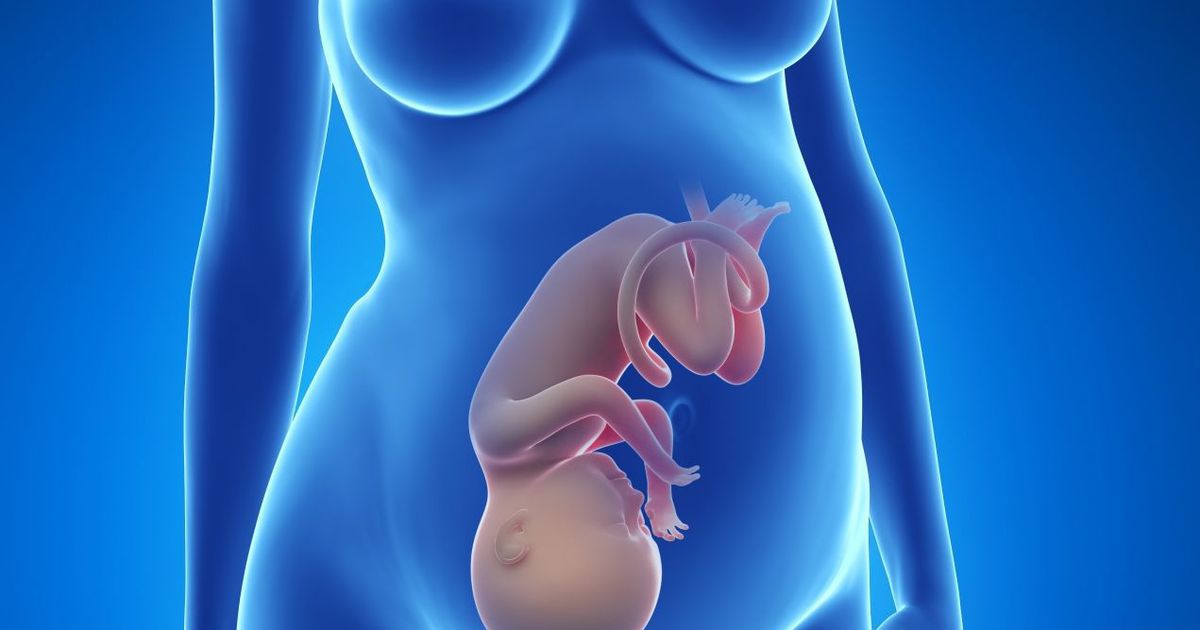

أسباب التشوهات الخلقية عند الجنين

وعن أسباب التشوهات الخلقية عند الجنين، كشف الدكتور هشام الشاعر، عن سبب الخلل الجيني والتشوهات الخلقية بالجنين والتي تأتي نتيجة لانفصال جزء من الكروموسومات الحاملة لجينيات الوراثية، والتصاقها بكروموسومات أخرى تحمل جينات وراثية مختلفة.

وحول التشوهات الخلقية للجنين تابع: الجدير بالذكر أن أكثر الأشخاص عرضة لإنجاب أطفال لديهم تشوهات وراثية خلقية هم الأقارب، حيث يوصى بتجنب زواج الأقارب لعدم حدوث خلل جيني وتشوهات خلقية بالجنين.

أسباب التشوهات الخلقية للجنين